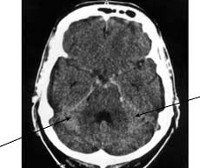

I60 Субарахноидальное кровоизлияние